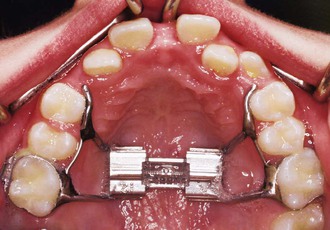

The protraction headgear force is applied via elastics to teeth or other devices supported by teeth and/or the palate. The primary aim is to transmit the force to the midface sutural interfaces. To achieve this, it is important to stabilize the maxilla as one unit (Fig. 16-1). In the primary dentition, it is advisable to use a cemented acrylic occlusal bite block or a removable acrylic plate with occlusal coverage (see Chapter 12). In patients with the mixed dentition and early permanent dentition, a removable acrylic plate (Fig. 16-2) should be used, supported by bands with headgear tubes on the molars or a rigid archwire with a palatal arch. Probably the best stabilization in patients with maxillary first molars is provided by a fixed rapid palatal expansion (RPE) device (Fig. 16-3). We prefer a Hyrax type of nonbonded device, as bonded RPEs (Fig. 16-4) interfere with the primary exfoliating teeth or teeth in the eruptive phase. Studies have also indicated that a simultaneous sutural expansion with an RPE at the start of protraction headgear treatment facilitates the anterior movement of the maxilla.19,20,26,27

Figure 16-2 Occlusal view of a removable intraoral stabilization appliance. The acrylic plate has a clasp that fits on a molar tube of a cemented band. This plate must be worn when the protraction appliance is in use.